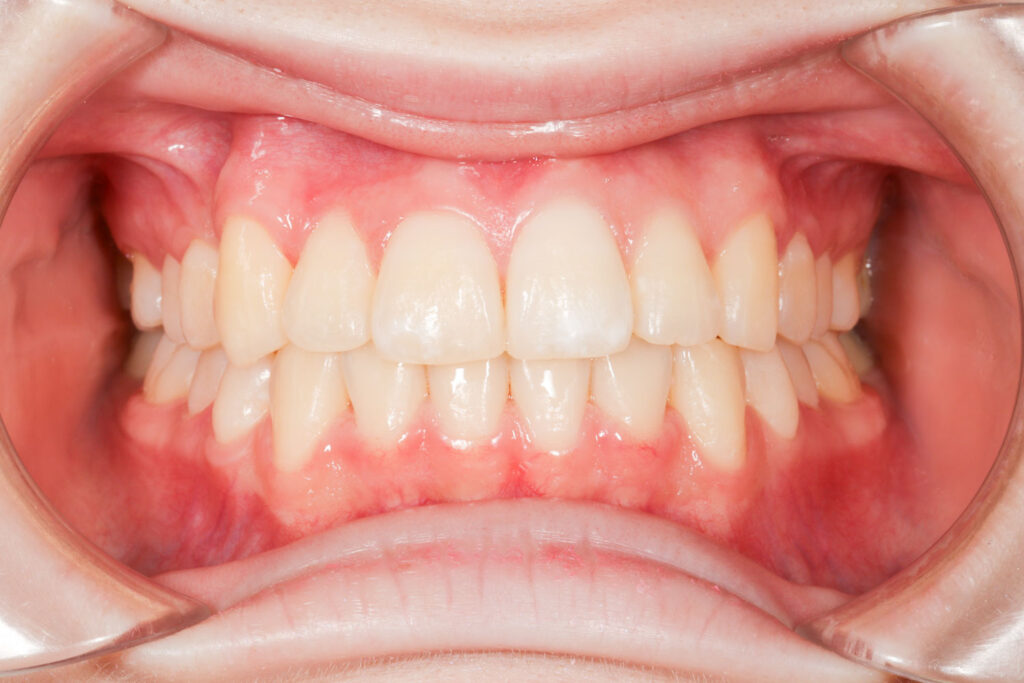

Before

After

年齢 10代

治療装置 表側の矯正装置(ホワイトコース)

治療内容 上下左右4本抜歯

治療期間 2年1か月

リスク 歯の移動に伴う痛み、歯肉退縮、歯根吸収、歯肉炎、虫歯

主訴 ガタガタが気になる

症状 叢生(ガタガタ)

治療回数 25回程度

総額費用 105万円程度